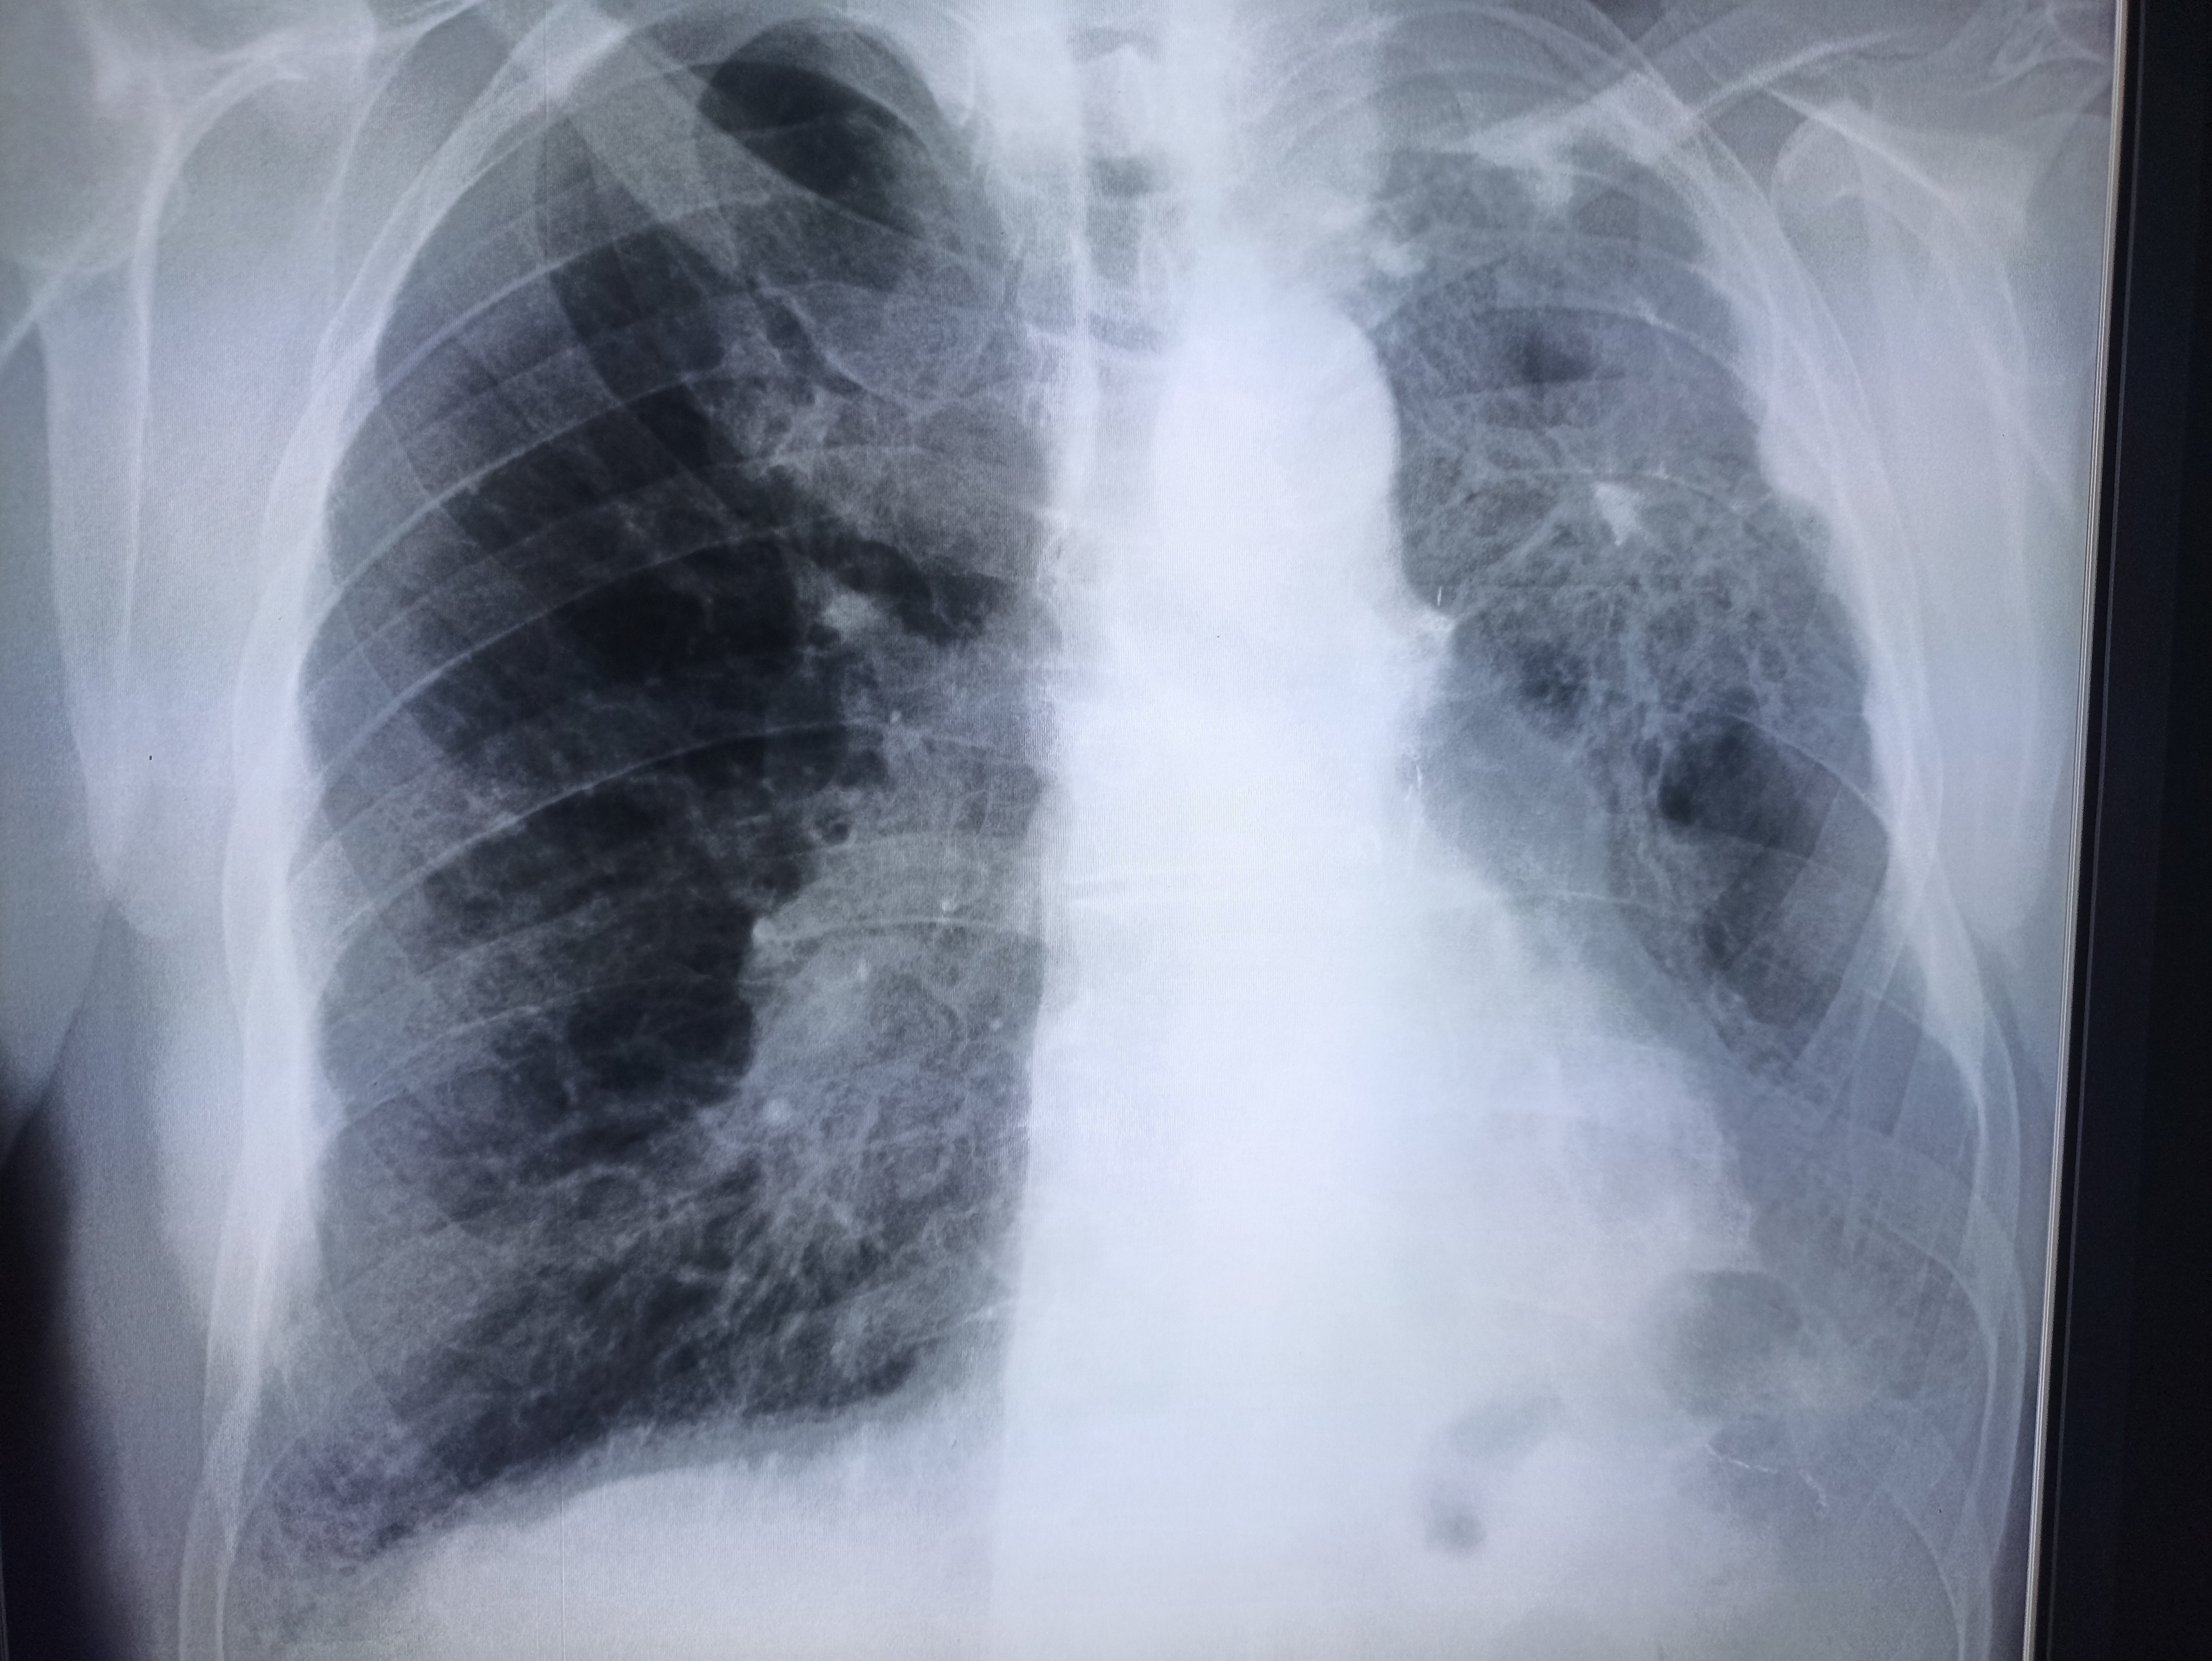

Здравствуй двачик, на прошлой неделе вышел из отпуска и уже дергается глазик, вчера сидел на работке пока поликлинику не закрыли и не все доделал. Не могу перестать кричать внутри головы! Потому мы с вами будем сегодня играть в доктора! Я буду вам показывать фоточки а вы угадывать пиздецомы! Што шпогнали! Найдите поломку!